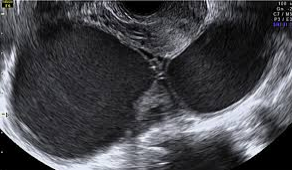

[서울와이어 김경원 기자] 난임을 초래할 수 있는 '자궁내막증'을 앓는 여성이 최근 5년간 48% 넘게 증가한 것으로 나타났다.

서종욱 국민건강보험 일산병원 산부인과 교수는 "자궁내막증은 반복적인 만성 골반 동통, 월경통, 성교통, 월경 직전 혹은 월경 중의 배변통, 생식 능력 저하 증상이 보일 때 의심해 봐야 한다"고 설명했다.